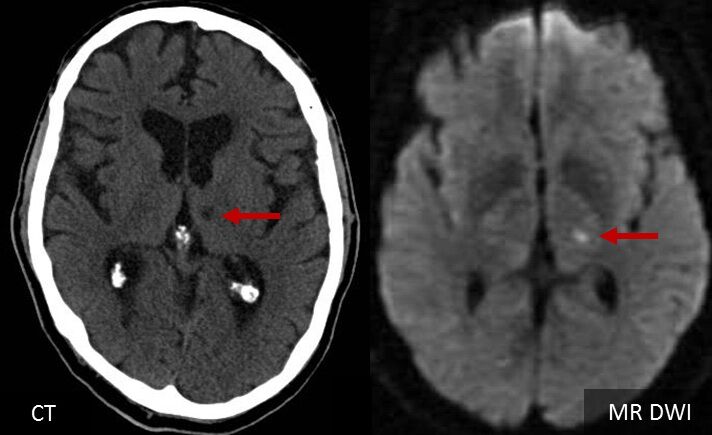

33.中風男性的核磁共振影像如下圖所示,最有可能的診斷為何?

(A) 小洞梗塞型中風(lacunar stroke)

小洞的範圍很小